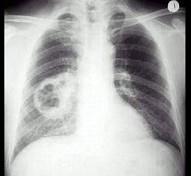

问题 男,54岁,咳嗽,伴胸痛2周,午后有低热,出汗较以前增多,胸片如图,最可能的诊断是 ( )

选项 A.肺脓肿 B.结核空洞 C.韦格肉芽肿 D.肺癌 E.肺大疱

答案 D